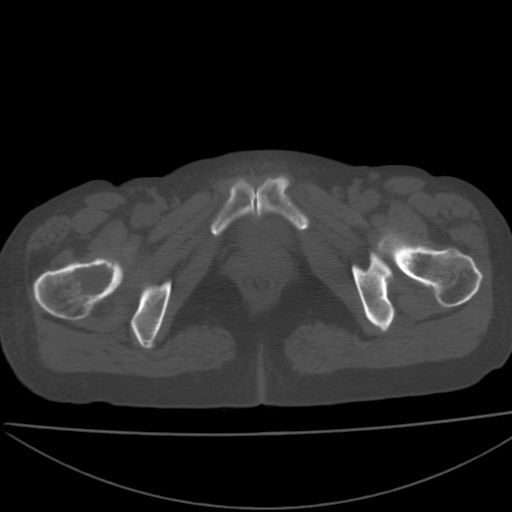

以下是引用xiaoniu在2008-9-6 8:22:00的发言:[br]右侧股骨颈囊性低密度,囊壁边缘硬化,中年妇女,首先考虑:骨囊肿。其次考虑动脉瘤样骨囊肿。[br][br][br][本贴已被 xiaoniu 于 2008-9-6 9:04:54 修改过]